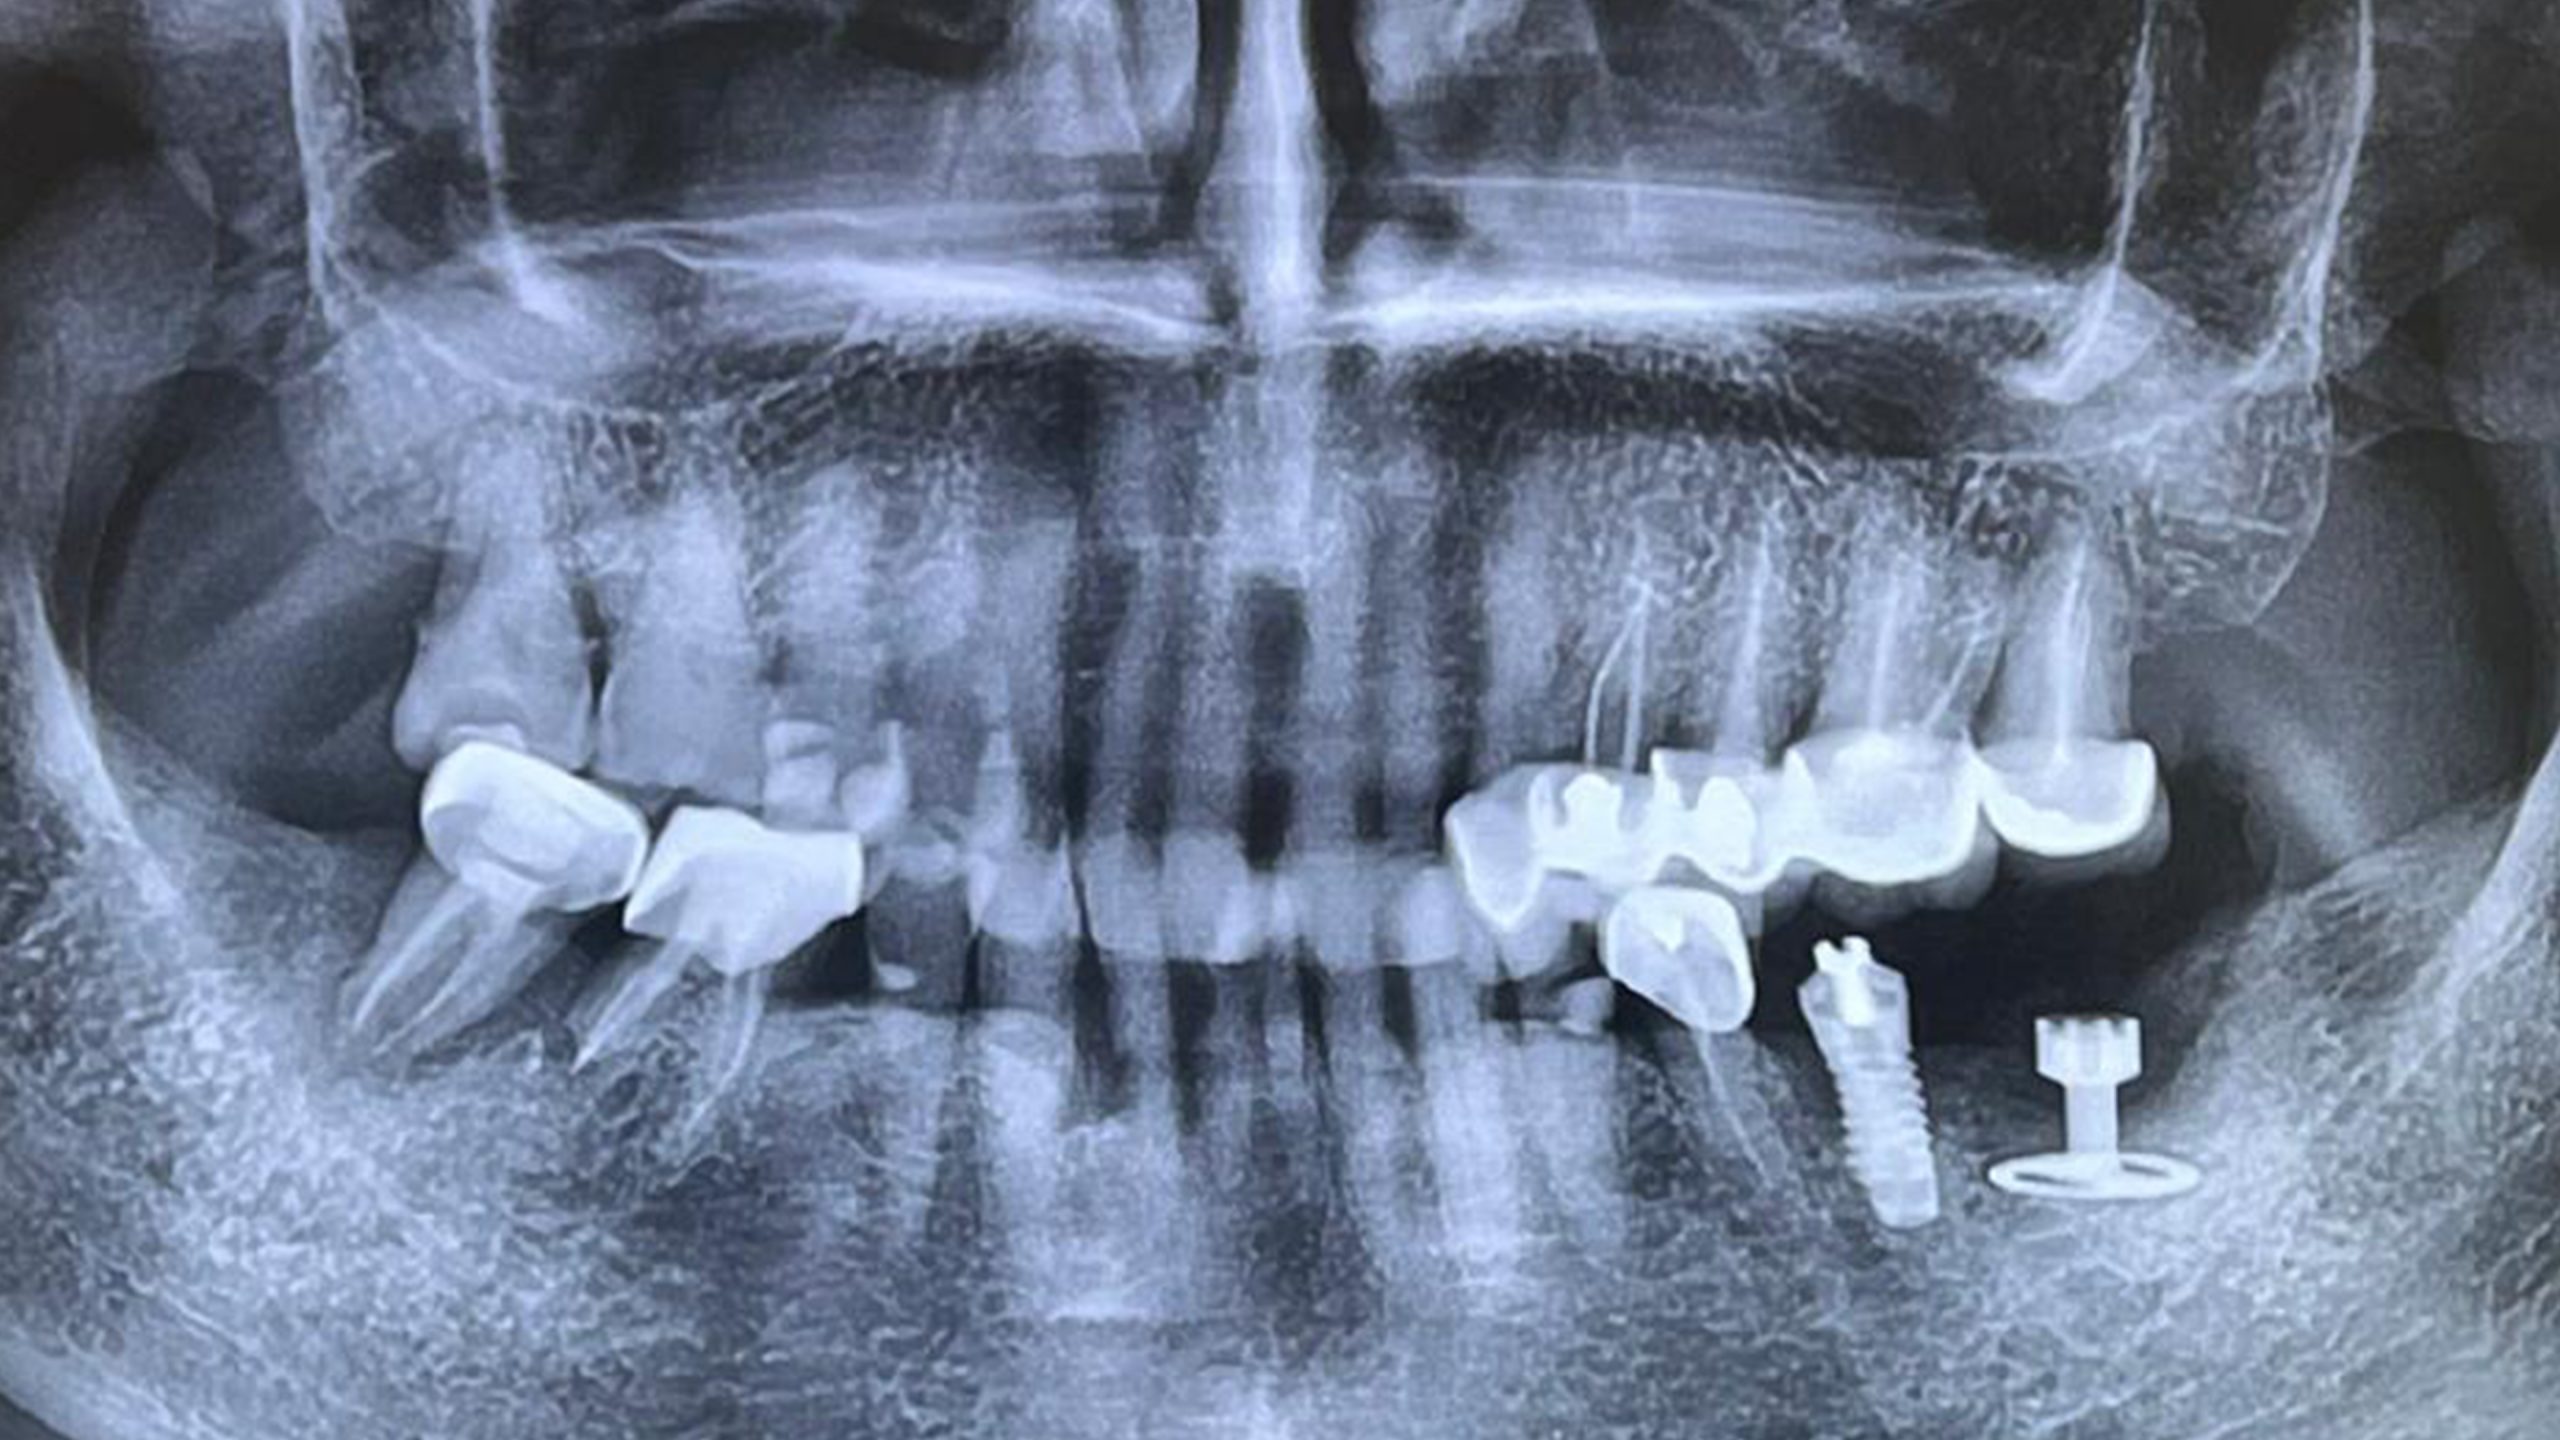

En amont, une activation ostéogénique avait été mise en œuvre, permettant d’initier un processus de régénération osseuse favorable.

Après une anesthésie loco-régionale, un lambeau de grande étendue a été réalisé afin d’obtenir une visibilité optimale pour placer l’implant.

Le diskimplant a été posé en enfouissement complet pour une durée minimale de six mois, étape indispensable à une ostéointégration fiable et durable.

La suite du protocole inclura la réouverture implantaire et la réalisation de l’empreinte prothétique en vue de la restauration définitive.